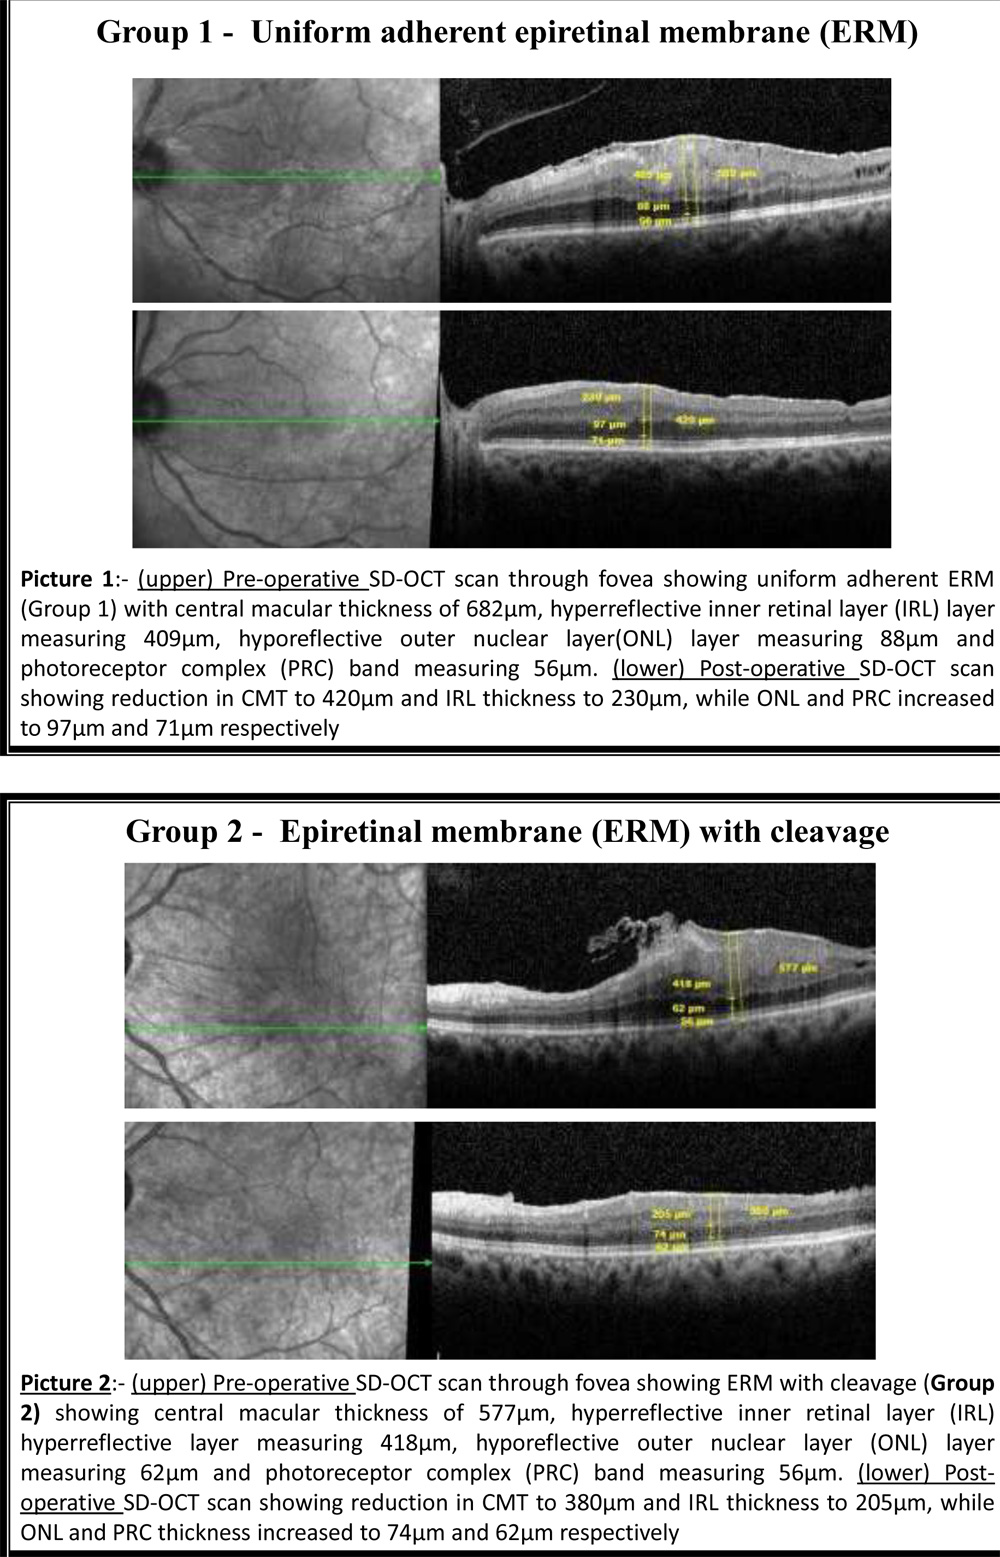

Additionally we had divided eyes under 2 groups according to the pattern of adhesion of ERM in macula:- Group 1- Uniform adherent ERM and Group 2- ERM with cleavage.

64 eyes of 64 patients with idiopathic ERM with mean postoperative followup up of 12 weeks were evaluated retrospectively. Mean age of patients was 64.34 years and there were 39 females out of 64 patients. Depending on patterns shown on SD-OCT patients were divided into 2 groups – Group 1 (uniform adherent ERM) (39 eyes) and group 2 (ERM with cleavage) (25 eyes). Other baseline characteristics and mean baseline pre-operative BCVA and SD-OCT parameters for both group 1 and 2 are shown in Table 1. Pre-operatively, Group 1 (uniform adherent ERM) had thicker CRT, thicker hyper-reflective IRL, thinner hypo-reflective ONL and thinner PRC as compared to Group 2 (ERM with cleavage). Postoperatively, Group 1 (uniform adherent ERM) showed significant decrease in mean CRT (607.22 to 420.80µm)(p<0.001) and mean IRL thickness (410.95 to 199.40µm)(p<0.001), while increase in mean ONL thickness (76.45 to 114.75µm)(p<0.001) and mean PRC thickness (65.87 to 69.03µm)(p<0.001). Group 2 (ERM with cleavage) showed significant decrease in mean CMT (566.21 to 417.33µm)(p<0.001) and mean IRL (358.79 to 198.83µm)(p<0.001) while increase in mean ONL (105.41 to 128.70µm)(p<0.001) and mean PRC (73.83 to 75.50µm)(p<0.001) (Table 2, Figure 2). Post-operatively, SD-OCT thickness for CRT and hyper-reflective IRL reduced by mean of 186.42µm and 211.55µm respectively in group 1 versus 148.88µm and 159.96µm respectively in group 2, while, hypo-reflective ONL and iso-reflective PRC thickness increased by mean of 38.3µm and 3.16µm respectively in Group 1 versus 23.29µm and 1.67µm respectively in Group 2. Change in SD-OCT thickness values were less in ERM with cleavage as compared to uniform adherent ERM (Table 3). 12 weeks post-operative SD-OCT showed persisting macular evagination in all the eyes, even when all retinal layers got restored within each retinal layer.